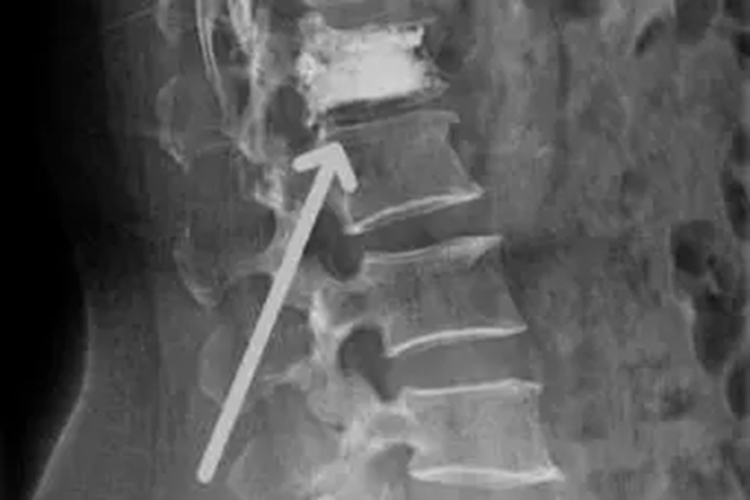

楔形骨折临床表现主要以局部症状表现为主,疼痛使运动功能受限,头颈部呈前倾僵直状态。棘突和棘间隙有压痛。并发神经压迫者,可表现出神经系统症状和体征。正、侧位X线片显示损伤的椎体前部压缩,整个椎体呈楔形改变;有时可表现小关节突骨折。